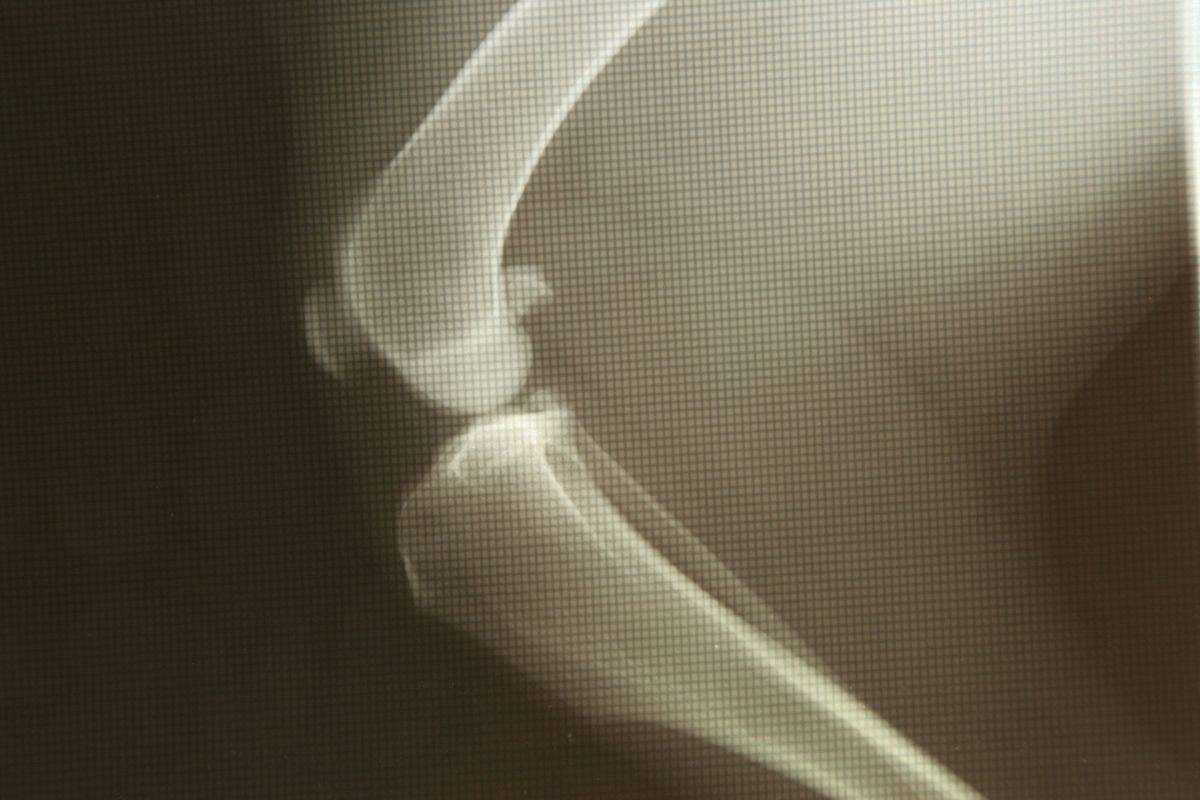

La principal causa de los problemas de movilidad es la osteoartrosis, enfermedad degenerativa que se caracteriza por la inflamación de las articulaciones y un intenso dolor crónico, y afecta a 1 de cada 5 perros. Esto hace que el perro tienda a moverse menos y gane peso, y sea necesario adaptar la alimentación para evitar el sobrepeso y obesidad, factores de riesgo en la aparición de problemas articulares. Como es un proceso progresivo es posible detectarlo en etapas iniciales si observan algunos signos.